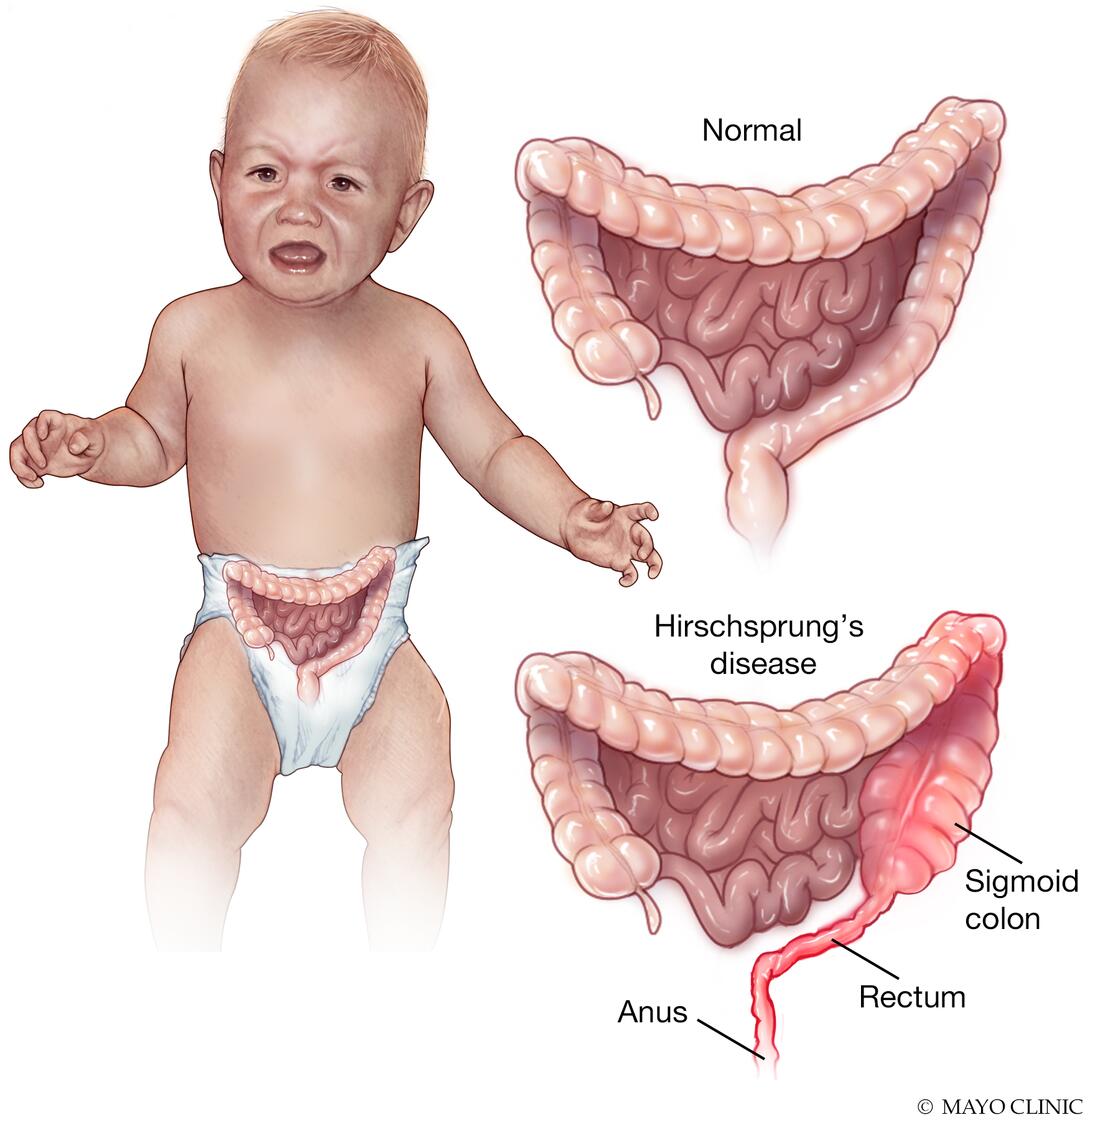

علائم در دوره نوزادی شامل عدم عبور مکونیوم (meconium) در مدت کوتاهی پس از تولد است. مکونیوم ماده چسبنده تیره رنگی است که به طور معمول هنگام تولد در روده وجود دارد و به عنوان اولین حرکت روده نوزاد پس از تولد دفع میشود. عدم دفع اولین مدفوع به مدت 24 تا 48 ساعت نشان دهنده HSCR است.

نوزادان مبتلا به HSCR اغلب دچار تورم شکم (اتساع)، درد شکم و استفراغ میشوند. نوزادان مبتلا یبوست دارند و اغلب افزایش وزن ضعیف و رشد آهسته را نشان میدهند.

طول روده ای که در HSCR تحت تاثیر قرار میگیرد میتواند متفاوت باشد. تقریباً در 80 درصد از نوزادان مبتلا، این روده بزرگ است که معمولاً کولون و رکتوم نامیده میشود که تحت تأثیر قرار میگیرند. رکتوم (rectum) آخرین قسمت روده بزرگ است و مقعد را به کولون سیگموئید (sigmoid colon) متصل میکند. گفته میشود نوزادانی که سلولهای گانگلیونی در رکتوم و کولون سیگموئید ندارند، به بیماری هیرشپرونگ «بخش کوتاه یا short-segment» مبتلا هستند.

در حالی که تقریباً 12 درصد از نوزادان دارای سلولهای گانگلیونی هستند که در بیشتر روده بزرگ از بین رفته اند و به عنوان بیماری هیرشپرونگ “بخش بلند یا long-segment” نامیده میشود، و تقریباً 7 درصد سلولهای گانگلیونی در کل روده بزرگ و احتمالاً بخشی از روده کوچک را ندارند که به این بیماری هیرشپرونگ “کولون کل یا total colonic” میگویند. در موارد نادر، سلولهای عصبی گانگلیونی در تمام طول روده بزرگ و کوچک وجود ندارد. به آن آگانگلیونوز کل روده (total intestinal aganglionosis) میگویند.

جمعیتهای آسیب دیده